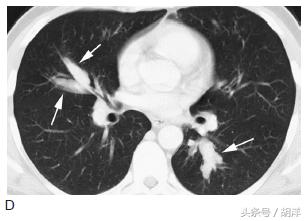

这种状态是身体本身为过敏体质,长期合并曲菌吸入,身体因为严重的过敏反应形成大量粘稠的粘液栓塞在气管中,很容易形成中央型支气管扩张,患者同时伴有哮喘样发作,很容易和哮喘混淆,但使用抗哮喘药物无效。

箭头所指为粘液栓和支气管扩张